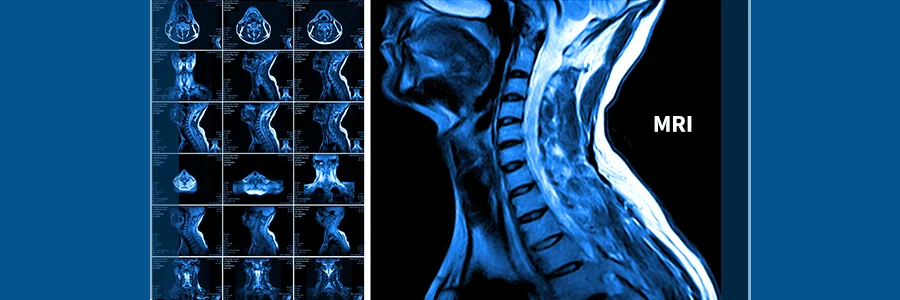

تشخیص آرتروز گردن با معاینه دقیق و استفاده از روشهای تصویربرداری انجام میشود. پزشک ابتدا علائم بیمار، سابقه پزشکی و نوع فعالیتهای روزانه را بررسی میکند. سپس با تستهای حرکتی، دامنه حرکت گردن و واکنشهای عصبی ارزیابی میشود.

برای تأیید تشخیص، از تصویربرداریهایی مانند اشعه X برای بررسی تغییرات استخوانی، MRI برای مشاهده بافت نرم و دیسکها، و در برخی موارد سیتی اسکن استفاده میشود. تستهای عصبی نیز در صورت وجود علائم فشردگی عصب انجام میگردد. تشخیص دقیق، اساس برنامهریزی درمانی مؤثر و انتخاب روش مناسب فیزیوتراپی یا سایر درمانهای غیرجراحی است.

MRI برای بررسی بافت نرم، دیسکها و اعصاب